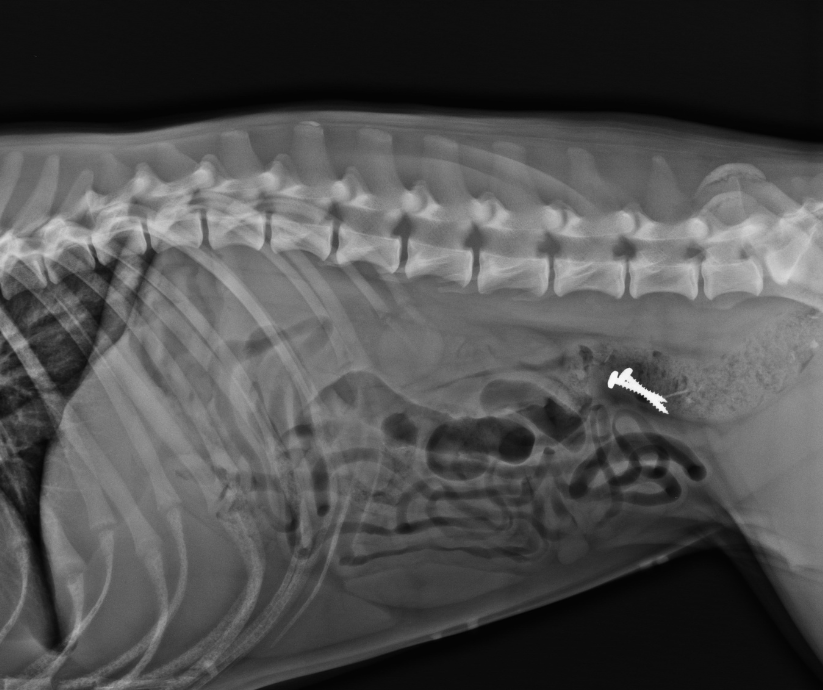

Badanie RTG jest jednym z najczęściej wykonywanych badań dodatkowych w diagnostyce weterynaryjnej – od wykluczania ciał obcych i płynu w jamach ciała, poprzez wykrywanie zmian w układzie kostno-stawowym, stomatologię aż po diagnostykę onkologiczną. Jak prawidłowo wykonać zdjęcie dobierając parametry ekspozycji i jak ułożyć pacjenta w konkretnych przypadkach, aby uzyskać diagnostyczne zdjęcie? Co robić, gdy pojawią się artefakty i jak ratować badanie bez zwiększania dawki? Tego wszystkiego i jeszcze więcej dowiecie się dzięki wyjątkowemu specjaliście-praktykowi na nadchodzącym szkoleniu.